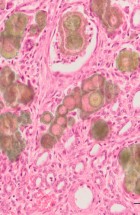

Делатност Одељења обухвата истраживачки и специјалистичко – стручни рад. Одељење се бави клиничком, патоанатомском, патохистолошком, имунохистохемијском и молекуларном дијагностиком обољења домаћих и дивљих животиња, као и патологијом репродукције. Рад на одељењу је организован кроз теренске и лабораторијске активности.

- Патохистолошка, цитолошка, имунохистохемијска и молекуларна дијагностика;